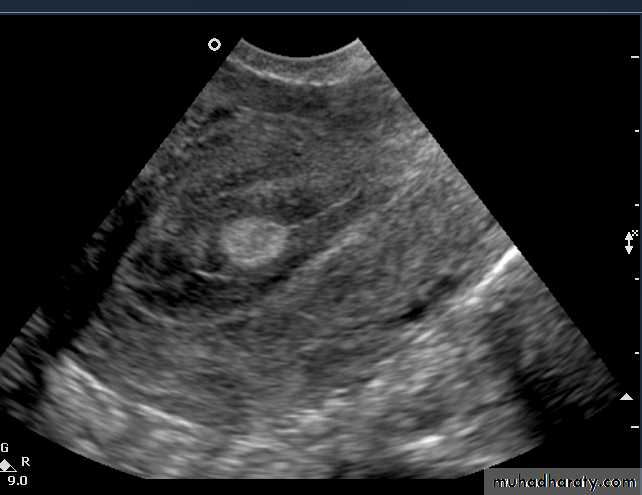

This young adult female patient was examined to evaluate the uterus and ovaries. She was under treatment for infertility and was using gonadotropins. Ultrasound images of the ovaries show grossly enlarged ovaries with large cysts (measuring 2.6 to 3 cms.) in both ovaries. These ultrasound findings are diagnostic of OHSS or ovarian hyperstimulation syndrome.

• Ovarian hyperstimulation syndrome (OHSS):

The ultrasound image again show hyperstimulated ovaries. Both ovaries are grossly enlarged and cystic.